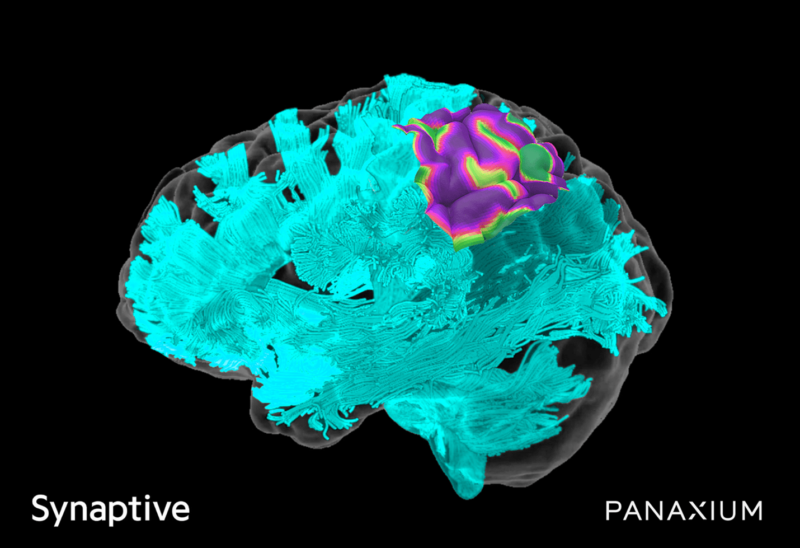

Synaptive Medical has entered into a joint-development partnership with bioelectronic medicine company Panaxium to integrate the latter’s iontronic electrocorticography (ECoG) platform into its Modus V robotic exoscope technology.

This integration is said to offer real-time intelligence on bioelectrical connections as well as decisive functional mapping information during procedures. It will preserve crucial brain tissues during resection, shorten procedure times, and enhance post-surgery outcomes, Synaptive Medical said.

“Synaptive already provides automated tractography segmentation for surgical planning with our imaging system, so the integration of Panaxium’s electrocorticography into Modus V is a natural next step for our technology and an exciting leap forward in the neurosurgical space.”

Additionally, Panaxium is commercialising its iontronic interfaces for use in monitoring and therapeutic neurostimulation applications. These include tumour excision surgeries and stroke recovery therapies including artificial intelligence (AI) assisted software for procedures.